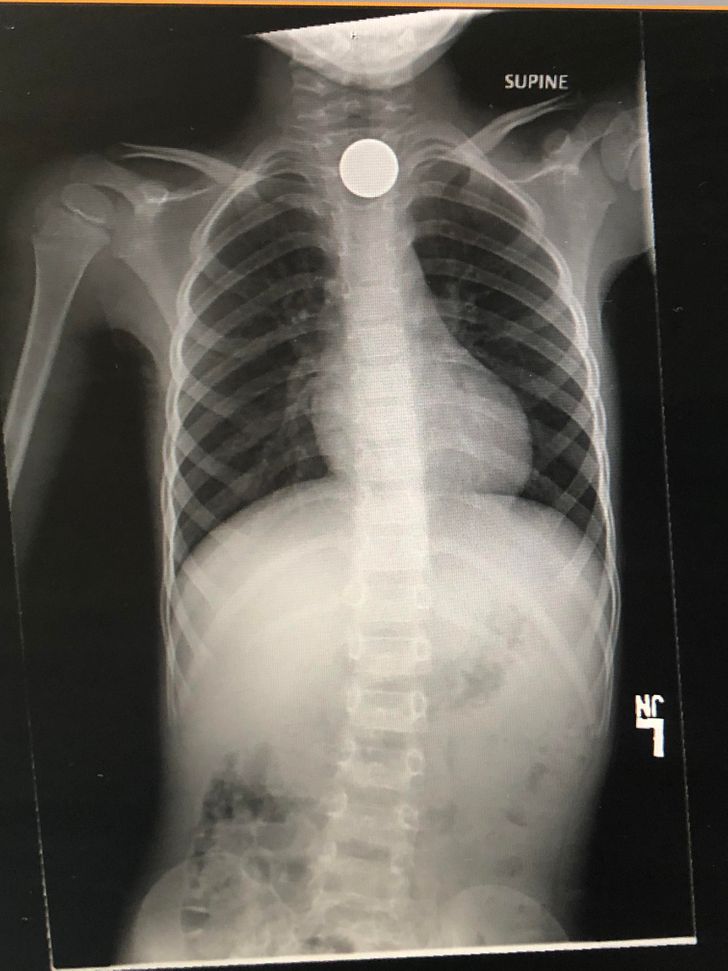

Az egyik nagy félelmem, hogy velem is megtörténik..